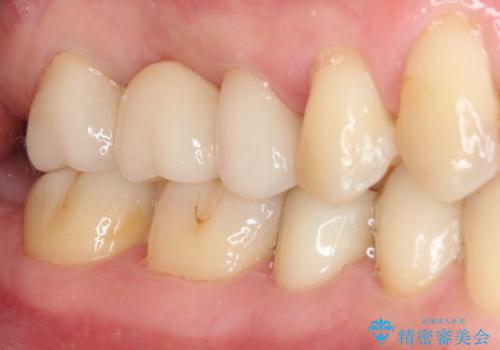

以前治療した詰め物が欠けた オールセラミッククラウンによる補綴

- 他院にて治療した詰め物が欠けてしまった事を主訴に来院された患者様です。

詰め物の範囲が大きく、部分的な詰め物では再び割れてしまうリスクが高いため、

オールセラミッククラウンにて補綴することとしました。

しみる症状はなくなり、見た目もきれいになり、とても満足されました。